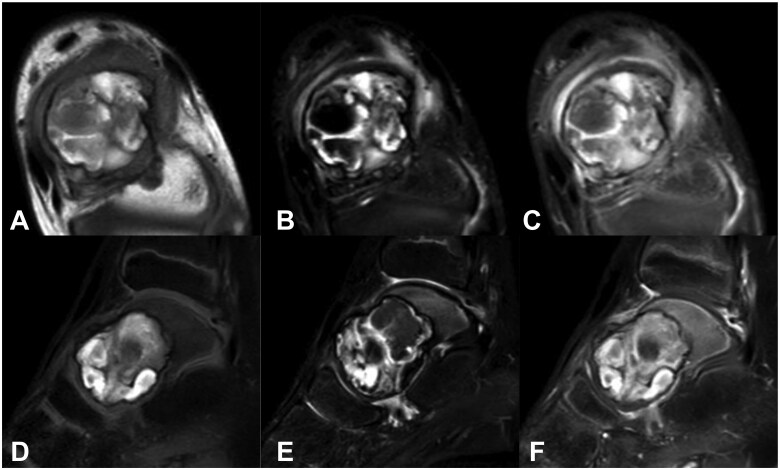

Aneurysmal bone cyst (ABC) is a locally destructive benign tumour-like condition of the bones with blood-filled cystic cavities. The talus is an extremely rare site for an ABC, with <20 reported cases till 2012 based on a PubMed database search. Aneurysmal bone cyst recurrence in the talus after curettage and bone grafting is extremely rare. To the best of our knowledge, no detailed reports of resection and adjuvant therapy with artificial bone packing of recurrent ABC of the talus have been published. We report a case of ABC in the talus of a 9-year-old boy. As the initial surgery consisted of only lesion resection and artificial bone (beta-tricalcium phosphate [TCP]) packing, local recurrence was diagnosed. Reoperation was performed 5 months after the initial surgery. The recurrent lesion was resected using a curette, and the bone cavity septum was shaved with a high-speed burr. Phenol-ethanol ablation was used as an adjuvant with artificial bone (beta-TCP) packing to prevent recurrence. No local recurrence was observed 36 months after the reoperation. This extremely rare case of resection and adjuvant therapy with artificial bone packing of recurrent ABC of the talus highlights the need for careful observation to assess the progression of ankle joint osteoarthrosis.

Abstract Image